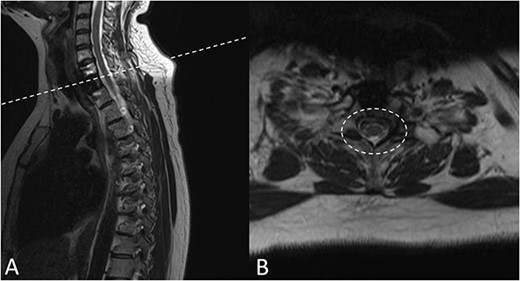

There were no surgical complications intraoperatively or postoperatively. A 3-day postoperative X-ray determined there was no mispositioning of the VBR and instrumentation (Fig. 3). There were no inpatient medical complications and pain was managed appropriately. Patient was discharged from hospital shortly after the operation and recovery. As outpatient, she did not complain of pain or wasn’t immobilized outside of the hospital. A 15-month follow-up MRI and 30-month follow up Positron emission tomography–computed tomography (PET-CT) maintained to show that the patient was tumour free (Figs 4 and 5). Lastly, upon assessment in clinic over 30 months, the patient was fully mobile and self-reported to be pain free, living independently and comfortably. There were no hardware related issues and there wasn’t any development of infection.

A 15-months postoperative follow up MRI Scan in May 2021. (A) Sagittal view of VBR cage indicating tumour free T2 body. (B) Transverse view of spinal compression reduction and resolved ESCC score.